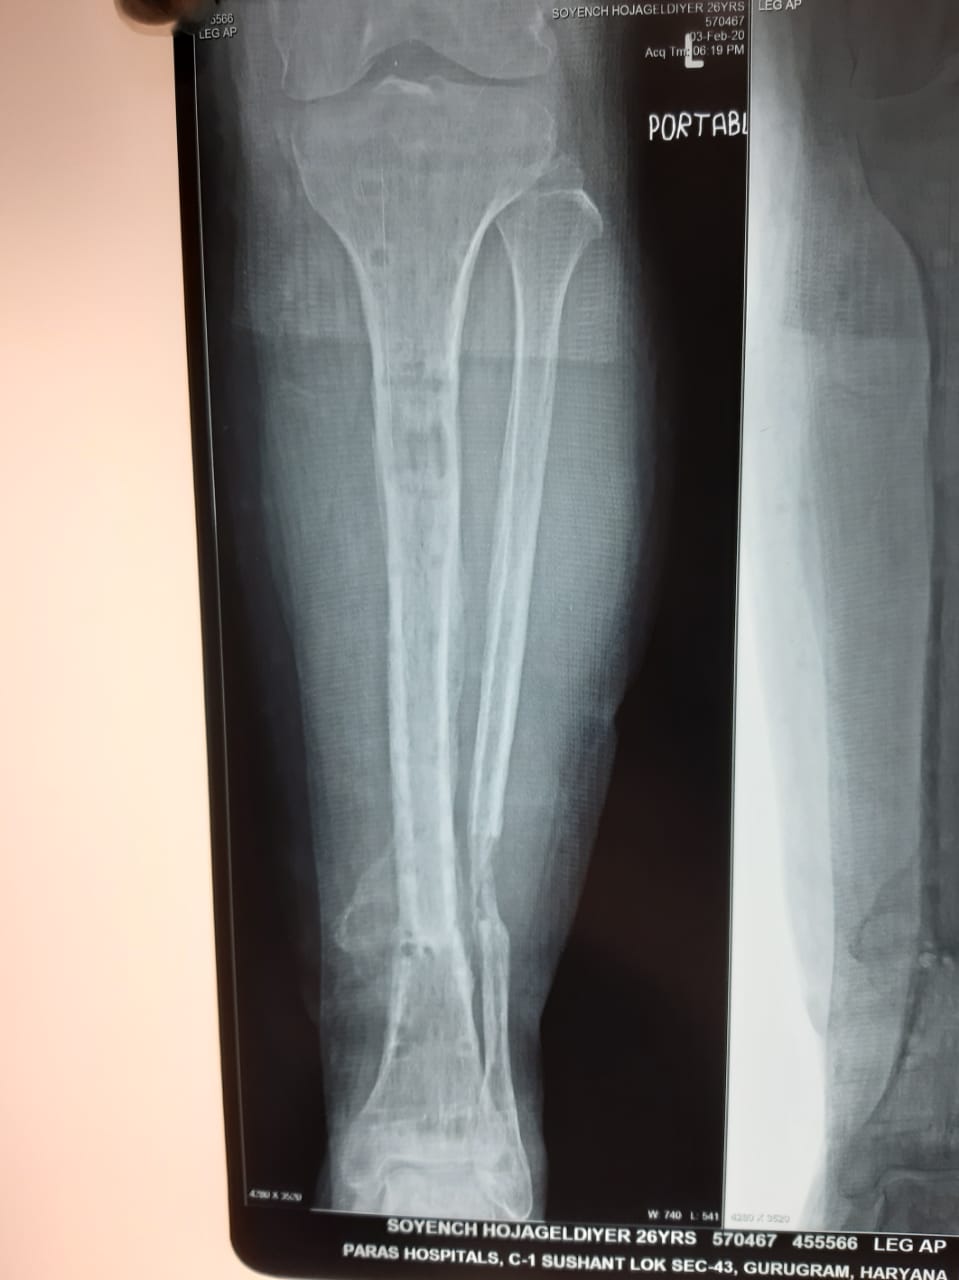

Another common scenario is one in which patient comes to us with open fracture of leg with an ununitied fracture with infection of bone and soft tissue previously elsewhere operated. In such cases the daunting task is to get rid of the infection and heal the fracture; here the technique of distraction osteogenesis (Ilizarov) comes to our rescue. First to get rid of the infection we get a pus culture done to assess the severity of infection and to assess the antibiotics that will be useful. During surgery we remove the dead and infected bone and soft tissues and bring the fracture ends together (docking), and apply the fixator (Monorail). Then we create a cut in the bone (corticotomy) and apply a distraction compression unit to help in creating a gap in the bone to allow distraction osteogenesis. Also antibiotic beads with the sensitive antibiotics are put at fracture site to kill the infection. Gradually over period of weeks the limb get lengthened to normal and infection is healed. The fracture also starts to heal by 3-4 months. The whole process might take upto 6 months.

Below are Xrays of one such case treated successfully by us over a period of 6 months.